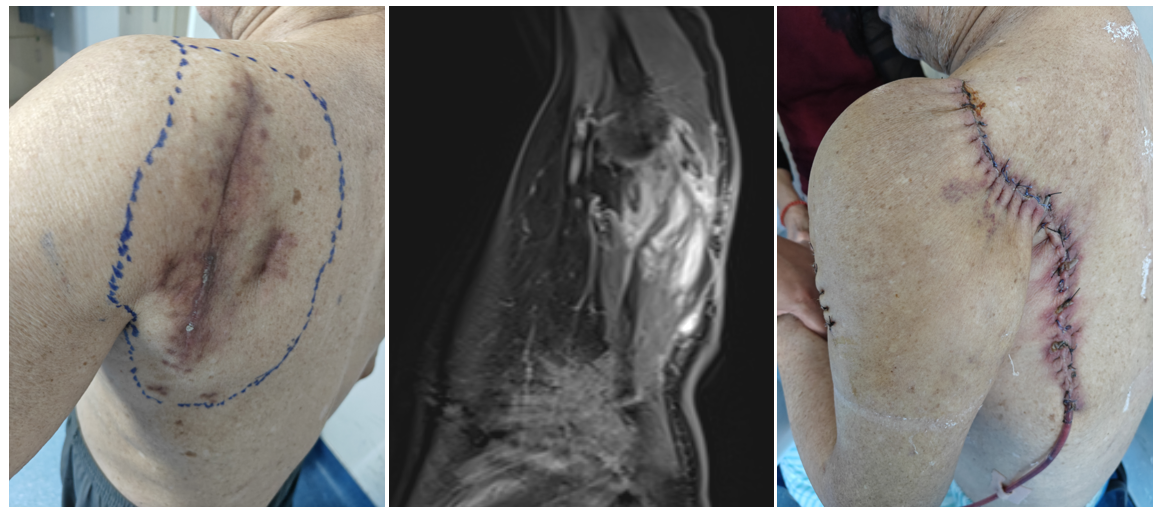

案例二 左肩胛区粘液纤维肉瘤(术后复发),转诊我院,在肩胛带全切除后进行屈肘功能重建手术。